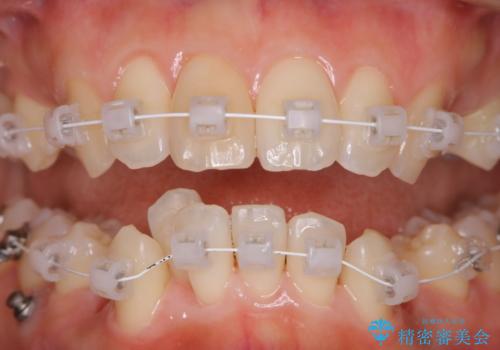

- メンテナンスの際に歯のステインが気になるということで今回はエアフローの機械を使用したクリーニングを行いました。

ステインが付着したままだと歯の表面がざらつき、普段のブラッシング時などに汚れが落ちにくくなります。定期的なメンテナンスの際にPMTC、エアフローを取り入れることをおすすめしております。